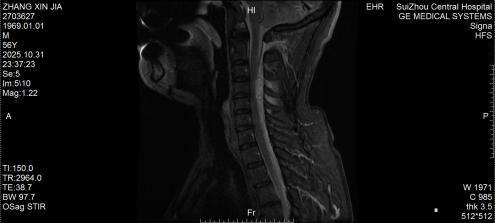

10月底的深夜,隨州市中心醫(yī)院急診醫(yī)學(xué)科來了一位特殊患者,突發(fā)劇烈頸痛伴雙手麻木,短短3小時內(nèi)肢體無力逐漸加重,連簡單抬臂都難以完成。脊柱外科團(tuán)隊緊急評估后行頸椎磁共振檢查,確診為自發(fā)性頸椎椎管內(nèi)出血—— 這是今年該院救治的第5例同類患者。好在急診手術(shù)及時清除血腫、解除神經(jīng)壓迫,患者術(shù)后恢復(fù)良好,無任何后遺癥,順利出院。

圖1:術(shù)前MRI見椎管內(nèi)積血壓迫脊髓

圖2:術(shù)后MRI見脊髓壓迫解除

2.確診金標(biāo)準(zhǔn):脊柱MRI能清晰顯示血腫位置和壓迫程度,是首選檢查;必要時通過DSA排查血管畸形等病因;